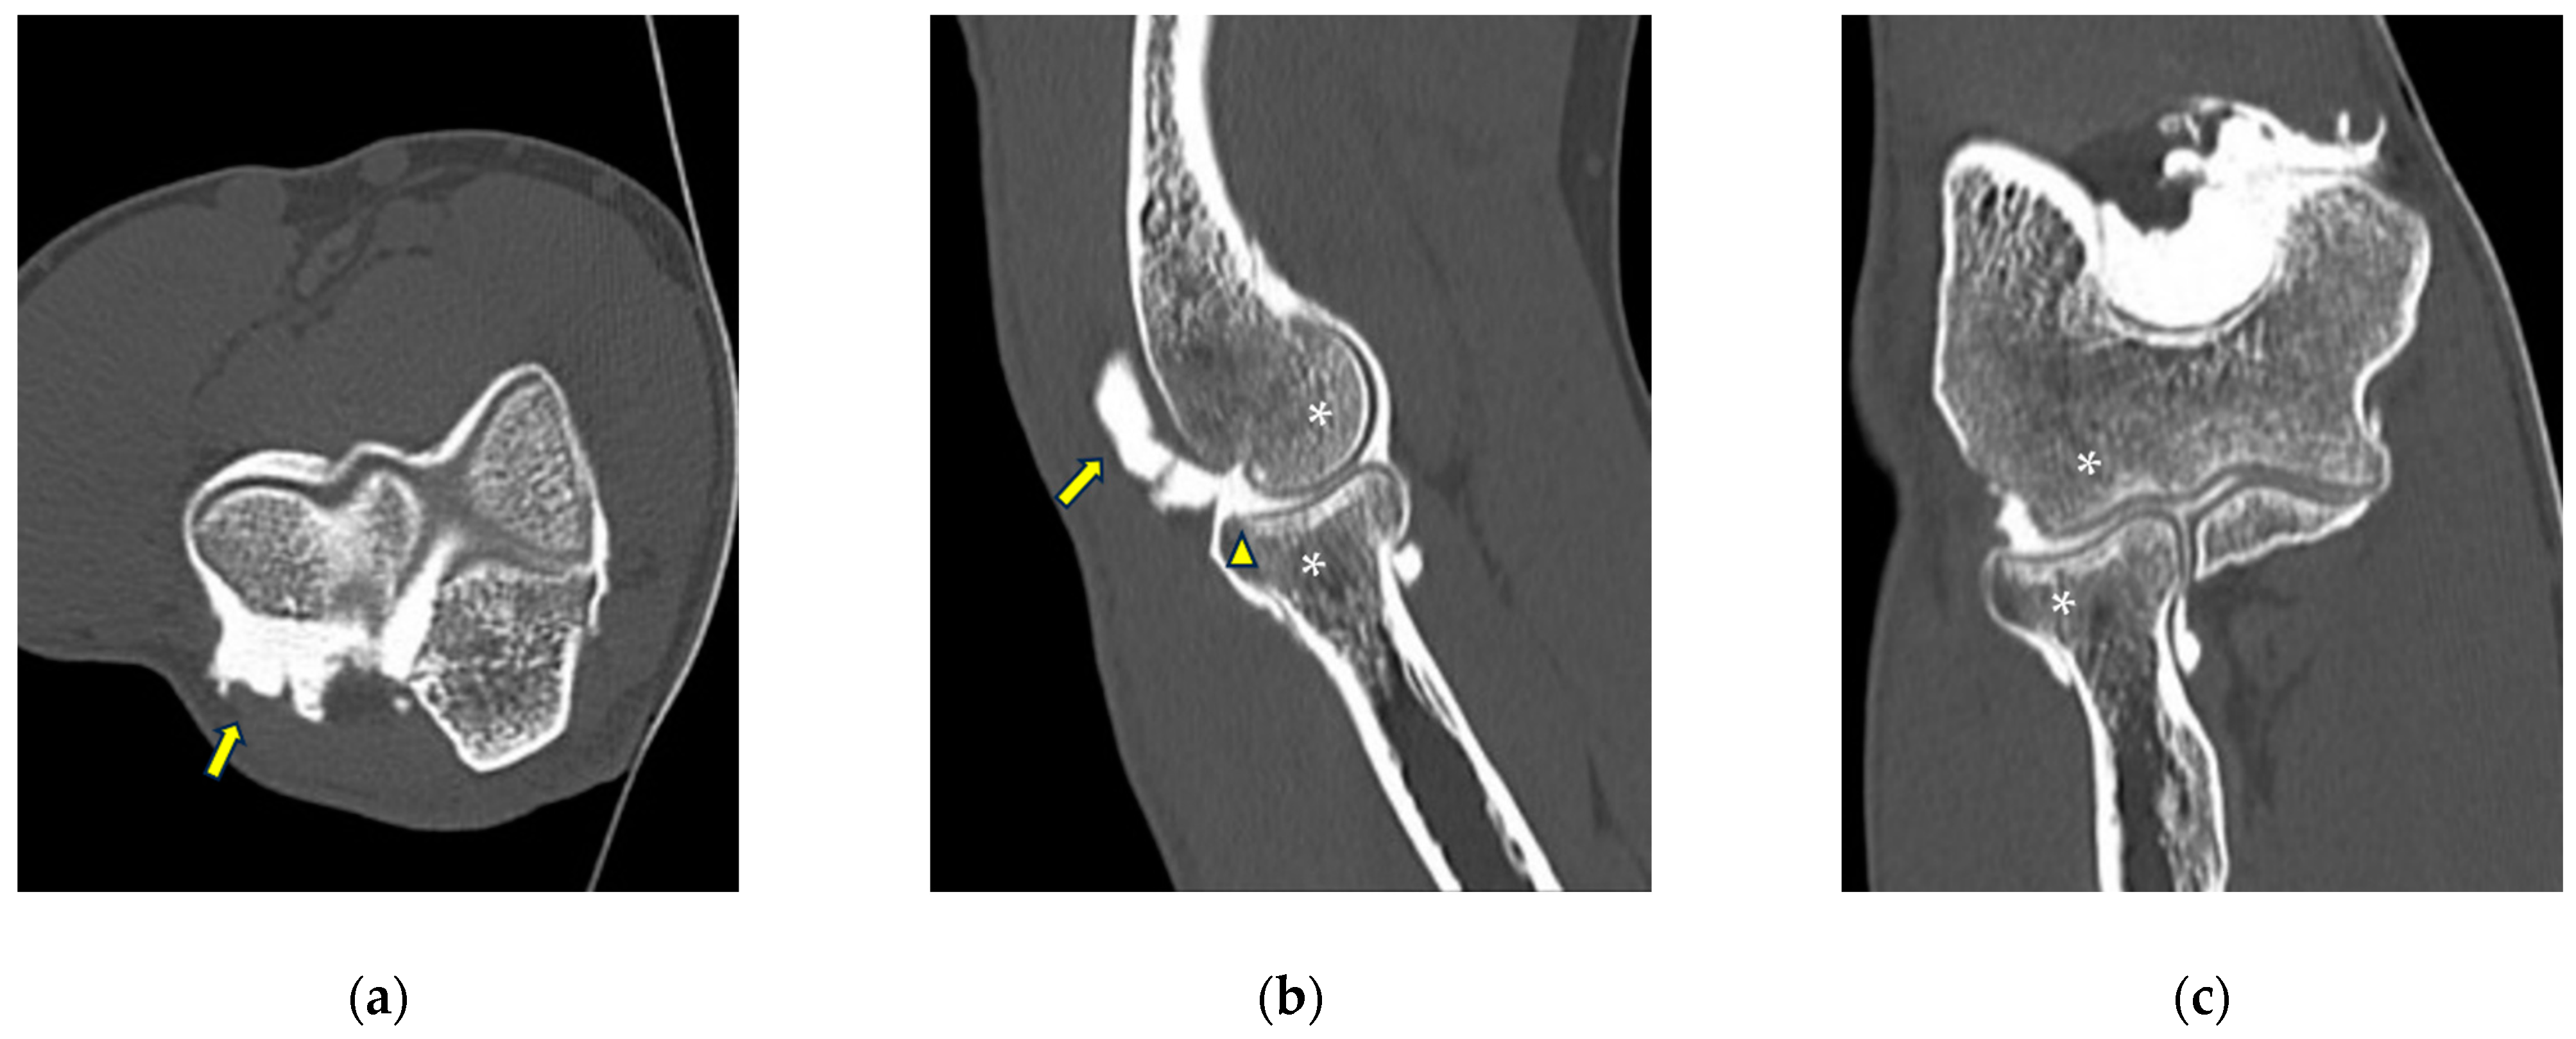

Figure 4.

CT-arthrography of a patient with rheumatoid arthritis. (a) Sagittal image shows pathological widening of the anterior humero-ulnar recess (asterisk), osteophytosis of the coronoid process (white arrowhead) and a distended posterior recess containing multiple non-calcific loose bodies compatible with secondary synovial chondromatosis (yellow arrowheads); (b) coronal image shows abnormal morphology and complete chondral erosion of both the radial head dish and lateral humeral condyle (yellow arrows).

Figure 6.

CT-arthrography of a professional motocross rider with chronic elbow pain due to repeated microtraumatism. (a,b) Axial and sagittal images show pathological widening of the postero-lateral recess (yellow arrows); (b,c) sagittal and coronal images show articular asymmetry of the humero-radial joint (asterisks), diffuse cartilage fraying and a full-thickness chondral defect (grade IV) of the posterior aspect of the radial head dish (yellow arrowhead).